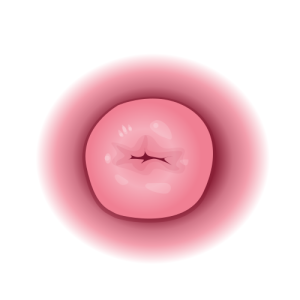

Inkondo y’umura (Cervix)

Ni igice gihuza nyababyeyi n’inzira y’umwana asohokeramo. Mu gihe cyo kubyara, inkondo y’umura igenda yaguka buhoro buhoro kugira ngo umwana abone aho anyura. Iyo itaguka neza, kubyara biragorana.

3. Cervix itaguka uko bikwiye

Umuyoboro w’inda ugomba kwaguka kugeza ku rugero rukwiye (santimeteri 10, uvuye kuri 0) kugira ngo umwana abone aho anyura. Iyo itaguka neza, kubyara biragorana, bikaba intandaro y’ibibazo bikomeye ku mubyeyi n’umwana.